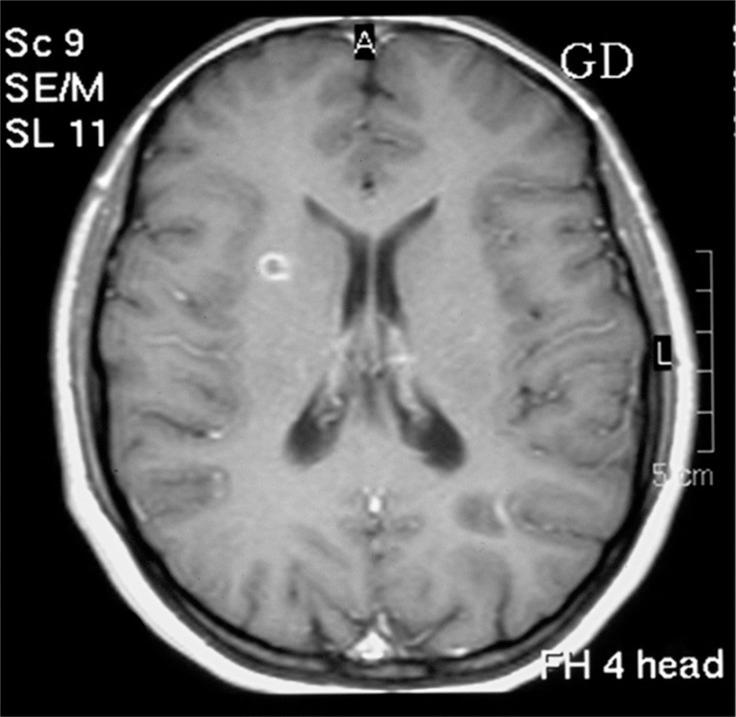

Morning glory syndrome (MGS) is a rare congenital optic disc anomaly characterized by a funnel-shaped, excavated optic disc surrounded by chorioretinal pigmentary disturbance. The main ophthalomoscopic feature of the MGS is enlarged optic disc with a funnel shaped scleral defect; elevated peripapillary chorioretinal pigmentation; and pale fluffy tissue of glial hyperplasia overlying the optic disc. Although most of the reported cases were isolated ocular abnormality, but it may occurs in association with other ophthalmic abnormalities such as cyst of the optic nerve atrophy, congenital cataract, microophthalmos, and aniridia. Craniofacial deformities such as cleft lip and palate, hypertelorism, dysplatic ears; renal abnormalities; and cardiac defects have also been reported with MGS. Herein, we present a case of MGS associated with multiple sclerosis - a rather unusual concurrence.

牵牛花综合征(MGS)是一种罕见的先天性视盘异常,其特征为漏斗状、凹陷的视盘,周围伴有脉络膜视网膜色素紊乱。MGS的主要检眼镜特征是视盘增大,伴有漏斗状巩膜缺损;视乳头周围脉络膜视网膜色素沉着升高;以及覆盖在视盘上的苍白蓬松的胶质增生组织。尽管大多数报道的病例为孤立性眼部异常,但它可能与其他眼科异常同时出现,如视神经萎缩囊肿、先天性白内障、小眼球和无虹膜。还报道了MGS伴有唇腭裂、眼距过宽、耳部发育异常等颅面畸形;肾脏异常;以及心脏缺陷。在此,我们报告一例与多发性硬化相关的MGS病例——这是一种相当不寻常的并发情况。